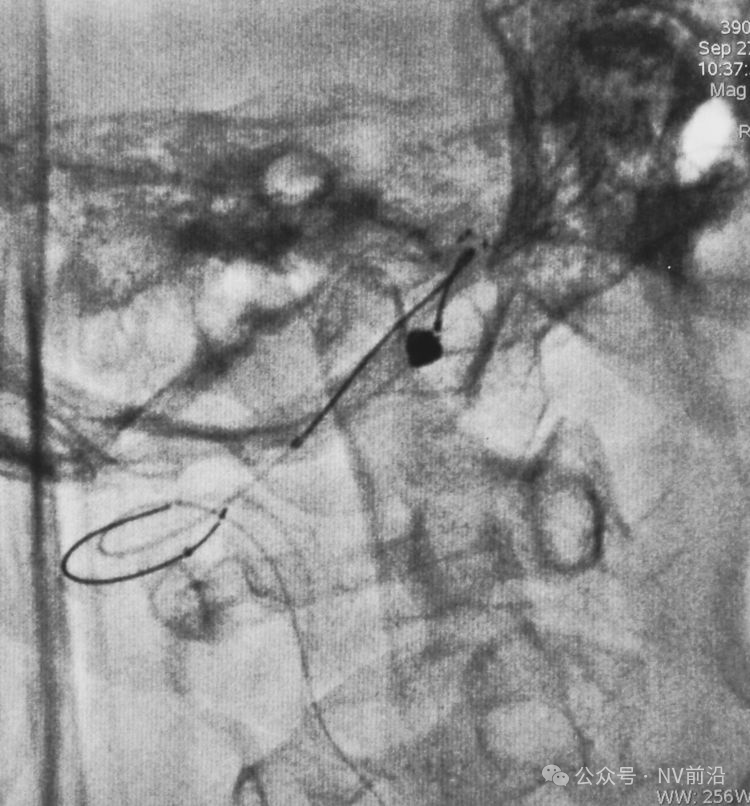

Solitaire 4×15支架(绿线)跨瘤颈半释放,压住微导管(红线)。

经微导管向瘤腔内送入首枚弹簧圈(QC-2-4-3D)。

跨瘤颈释放Solitaire 4×20支架(蓝线),压住微导管(红线),在支架保护下经返折的微导管送入弹簧圈填塞瘤腔。

依次送入QC-2-4-3D,2-3-Helix,1.5-2-Helix,1.5-2-Helix四枚弹簧圈,最后一枚弹簧圈将管头(箭头)顶出瘤腔。